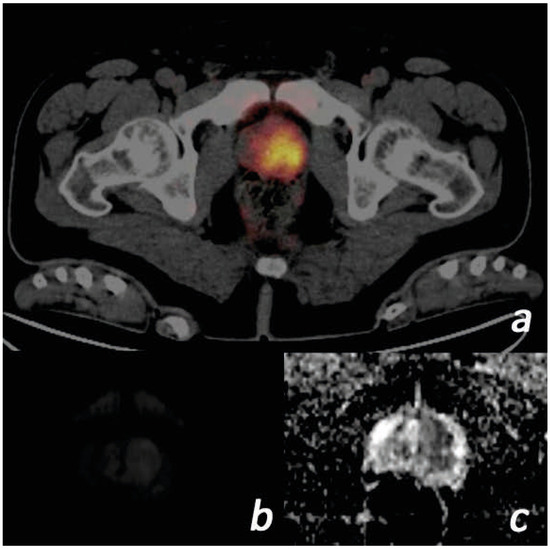

After correlation of the index/dominant lesion with Ga-68 PSMA PET/CT fusion images (Figure 1), diffusion-weighted images and ADC maps were evaluated. The mean ADC measurement (×10−3 mm2/s) of the index/dominant lesion was calculated from ADC maps by two radiologists, one of whom had 20 years and the other 4 years of experience in abdominal radiology. The region of interest (ROI) determined for the measurement was 25 mm2 for standard purposes. Due to the possibility that ADC measurements were subjective, intraobserver and interobserver agreement were investigated. The means of all measured ADC values were used in the statistical analysis.

Figure 1. Images of a 57-year-old male patient. (PSA = 117.1 ng/mL, free PSA = 36.2 ng/mL, Gleason score = 4 + 3, ISUP grade = 3) (a) Tumor with SUVmax value of 16.38 on the left in the prostate gland transition zone on Ga-68 PSMA PET/CT focus is shown. (b) The lesion is slightly hyperintense on diffusion-weighted b = 800 images. (c) ADC images are markedly hypointense. The ADC value was measured as 0.40. ADC, apparent diffusion coefficient; ISUP, International Society of Urogenital Pathologists; PET/CT, positron emission tomography/computed tomography; PSA, prostate-specific antigen; PSMA, prostate-specific membrane antigen; SUVmax, standardized uptake value.